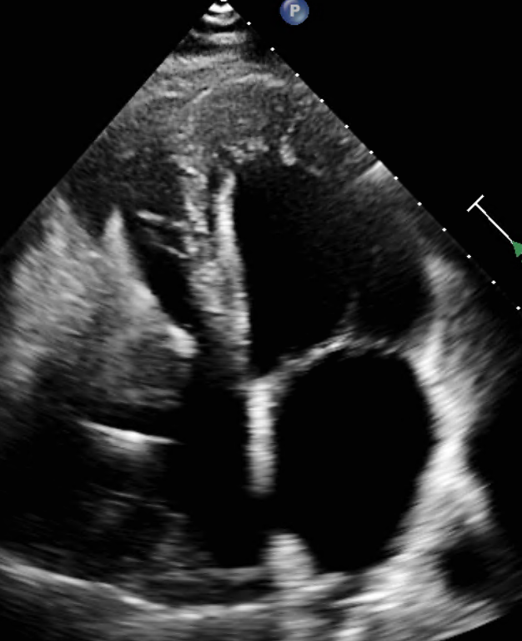

Echocardiogram

Example showing thickening of the apex of the left ventricle.